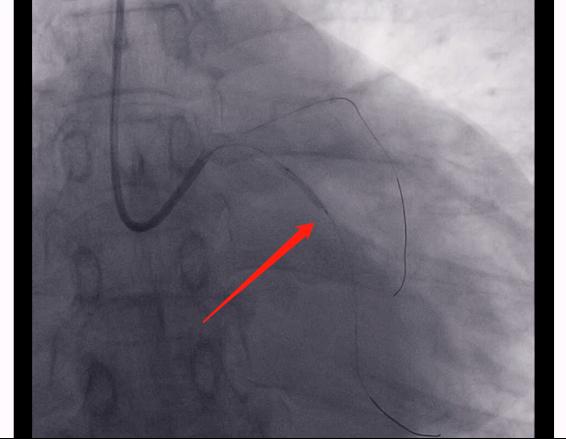

如图,是右侧的冠脉造影。

病人的右冠也是闭塞的,并且一开始就闭掉了。

4.对于冠心病患者,我们只有进行规范化的、综合性的康复的治疗,才会有一个良好的结果。(图片是患者打通闭塞血管,放置了两根支架的一个情况。同时我们还可以看到右边这根血管闭塞出现的一个侧枝循环,也就是左侧的这些血管,和右侧血管远端联通的一个影像,这就是自身进行的侧支循环的建立。)